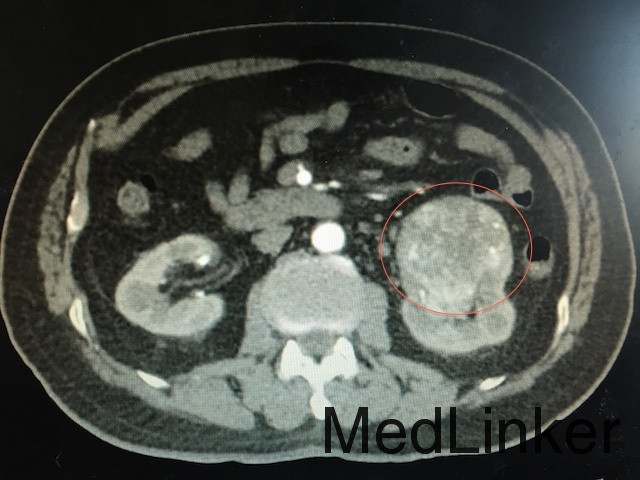

查体:左肾区叩痛可疑阳性 辅助检查:泌尿系CT平扫+强化如下图所示:左肾下极可见软组织密度团块影,突出肾轮廓并累及肾窦,大小约为6.6*6.1*5.7cm,动脉期呈不均匀强化,可见左肾动脉分支血供。

诊断:肾占位(肾恶习肿瘤可能性大) 治疗:肾癌根治术

随访:肾及肾周包膜切除,病理回报为肾透明细胞癌 讨论:肾恶性肿瘤主要与肾错构瘤鉴别,后者B超可见脂肪密度高回声,CT平扫为脂肪密度,CT增强强化比肾恶性肿瘤更明显。